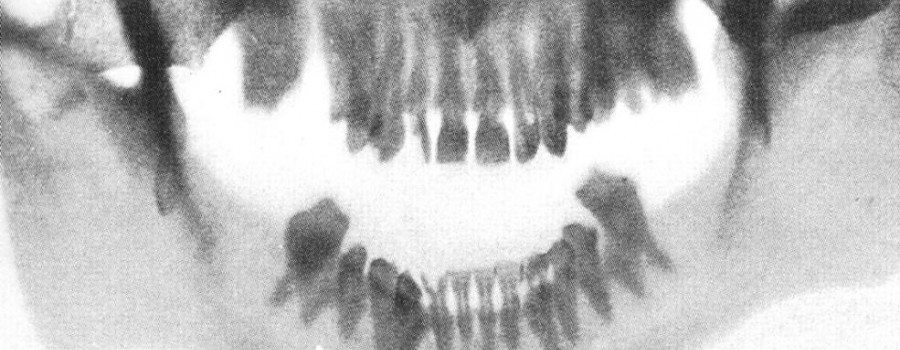

Das im Volksmund bekannte Rapunzel-Syndrom (Trichophagie) beschreibt ein zwanghaftes Verhalten des Patienten. Es beinhaltet das Verschlucken sowie das Essen der eigenen Haare über einen längeren Zeitraum.